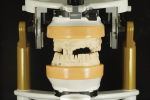

Upon receiving the framework, the prosthodontist tried it in the patient's mouth to ensure a passive fit with the angle correcting rings (Sphero Block Micro®) (Figure 16 and Figure 17). After the framework's fit was verified, he mounted the RPD framework on the articulator to set anterior denture teeth (Creapearl®, Willi Geller Creation, creation-willigeller.com).

After obtaining the patient's approval for esthetics, the first author set the posterior denture teeth with group function on both sides and processed the denture base with injectable heat-cured acrylic resin (IvoBase®, Ivoclar Vivadent, ivoclarvivadent .com) (Figure 18 and Figure 19). Finally, the prosthodontist provided the implant-assisted RPD by incorporating two clear nylon inserts chairside using a cold-cure acrylic (Figure 20).